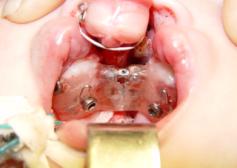

Clinical

application of microimplants. All patients (23 children) with congenital bilateral

cleft lip and palate with third degree of

intermaxillary bone deformation

the presurgical orthodontic treatment was executed by using of

microimplants. At the begining, the microimplants have been used in 6 patients

for intraosseous fixation of

supramaxillary non-removable orthodontic appliances (Fig. 4). Others 17 children

with such pathology used the microimplants as supporting elements of

orthodontic appliances (Fig.5).

Within

children's clinic conditions of maxillo-facial surgery under the general

anesthesia, 6 patients have been installed by supramaxillary non-removable

devices that are fixed to the bone by using of microimplants (Figure). For this

purpose the holes in the projection angle of 45 °C to the top of the comb of

the alveolar process were prepared beforehand on the fixed fragments (two side

and maxillary bones). At the same time the both sides fragments were connected

by a V-shaped orthodontic screw for expansion of the side fragments of the

upper jaw. This structure of the apparatus used for the expansion of the side

fragments of the upper jaw and for repositioning the intermaxillary bone in the

correct position, forming the alveolar arch.

4 5

Fig. 4 -patient À-v Ñ. , 4 months., bilateral cleft lip and palate after fixation supramaxillary non-removable device to the upper

jaw fragments and to the intermandibular bone by

microimplants.